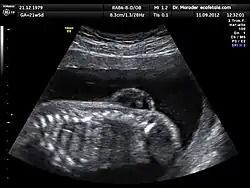

L’échographie est la principale et la plus courante des méthodes de diagnostic prénatal. En France, il est ainsi obligatoire de pratiquer trois examens échographiques[9], à 12, 21, puis 33 semaines d’aménorrhée.

Cette technique permet, grâce à l’utilisation d’ultrasons, de voir le bébé par image de synthèse. Elle permet de contrôler l’avancée de la grossesse et détecte un certain nombre de malformations ou de signes avant-coureurs de maladies génétiques. Par exemple, cet examen est l’un des trois composants du « triple test » en vue du dépistage de la trisomie 21, car il permet la mesure de l’épaisseur de la nuque, signe d’appel de cette affection[10].

Le premier examen échographique permet d'exclure des malformations de l'utérus et des tumeurs génitales, de déterminer le nombre de fœtus, de constater la vitalité du/des fœtus, de vérifier l'âge gestationnel en mesurant la longueur vertex-coccyx, de mesurer l'œdème nucal du fœtus et de vérifier la morphologie (tête, thorax, extrémités).

Le 2e examen a pour but principal l'observation de l'anatomie fœtale, afin de montrer directement des malformations fœtales ou de les suspecter à l'aide d'indices indirects. La quantité de liquide amniotique est aussi évaluée, ainsi que la position et la morphologie du placenta[11].

Le 3e examen doit permettre d’évaluer le développement fœtal, le fonctionnement régulier du placenta ainsi que le positionnement exact du fœtus et les problèmes éventuels de cordon ombilical en vue de l’accouchement[12].